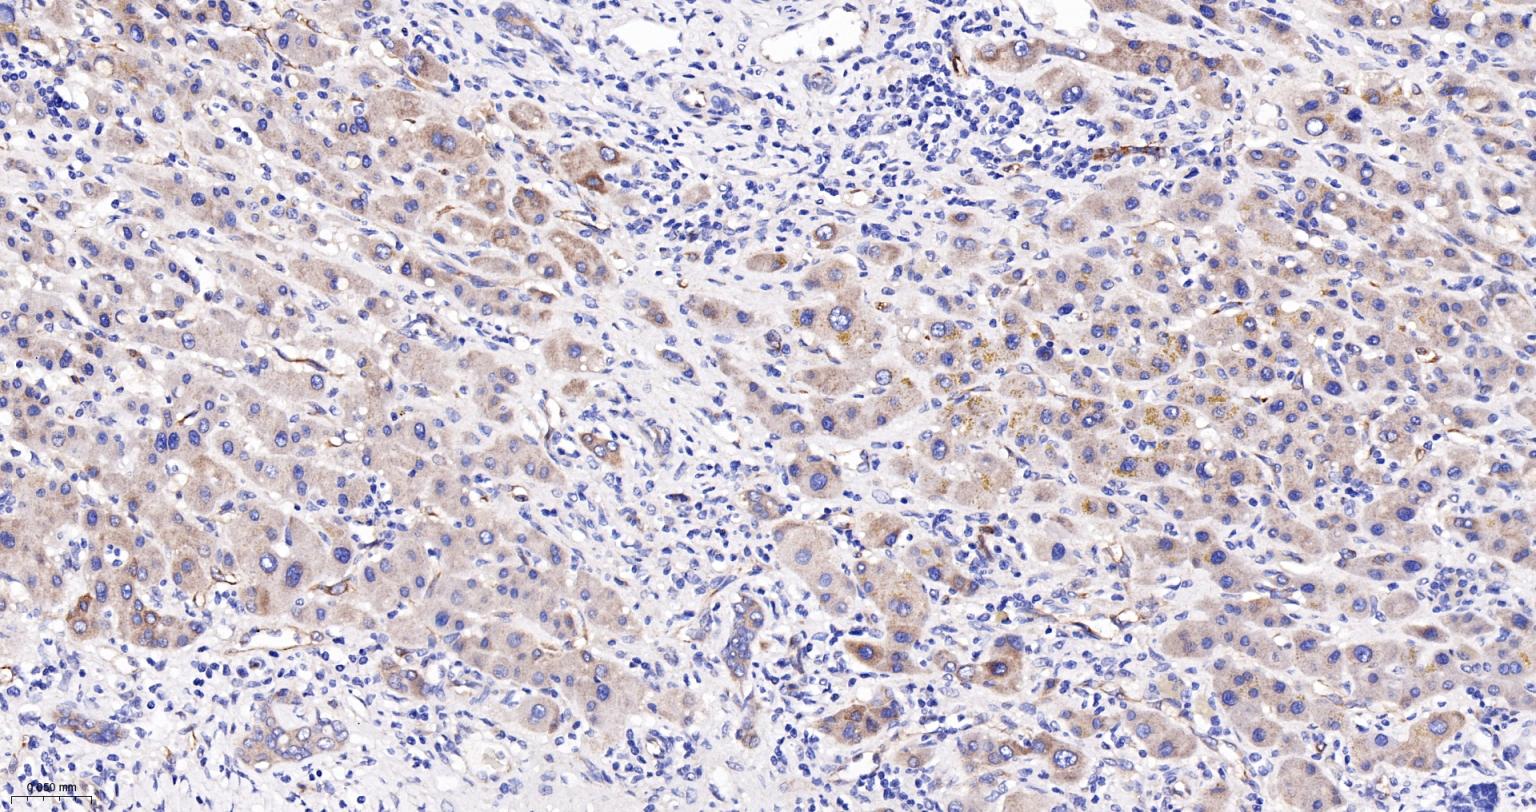

Paraformaldehyde-fixed, paraffin embedded Human Pancreatic Cancer; Antigen retrieval by boiling in sodium citrate buffer (pH6.0) for 15 min; The section was incubated with Radixin Monoclonal Antibody, Unconjugated (bsm-61253R) at 1:200 overnight at 4°C, followed by conjugation to the bs-0295G-HRP and DAB (C-0010) staining.

Paraformaldehyde-fixed, paraffin embedded Human Pancreas; Antigen retrieval by boiling in sodium citrate buffer (pH6.0) for 15 min; The section was incubated with Radixin Monoclonal Antibody, Unconjugated (bsm-61253R) at 1:200 overnight at 4°C, followed by conjugation to the bs-0295G-HRP and DAB (C-0010) staining.